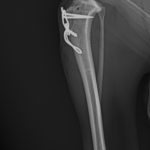

膝蓋骨内方脱臼G3に前十字靭帯断裂併発

5歳のToy Poodleさん。子犬の時から膝蓋骨内方脱臼(パテラ)があったそうですが、今まで特に症状もなく元気に暮らしていました。しかし、ここ1ヶ月で、跛行が目立つよになってきたとのことでかかりつけ医を受診しました。前十字靭帯断裂を併発してしまったようです。ドロアーサイン、ファットパッドサイン、脛骨圧迫試験が陽性でした。そのため、膝蓋骨内方脱臼を整復すると同時に、大腿骨遠位にアンカースクリューと脛骨近位にホールを開け人工靭帯法(ラテラルスーチャー)で安定化させました。